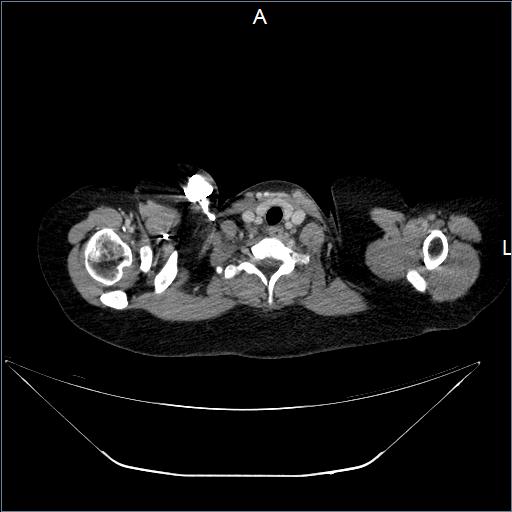

Mujer de 22 años con antecedente de linfoma multitratado, con recaídas y recidivas de la enfermedad. Ingresa en esta ocasión por la presencia de “síntomas B” y adenopatías cervicales.

A la EF: adenopatías cervicales bilaterales y hepato-esplenomegalia. Sus exámenes de laboratorio mostraron: Hb 10.6, leucocitos 5,180, NT 3720 y plaquetas 10, 002.

TAC